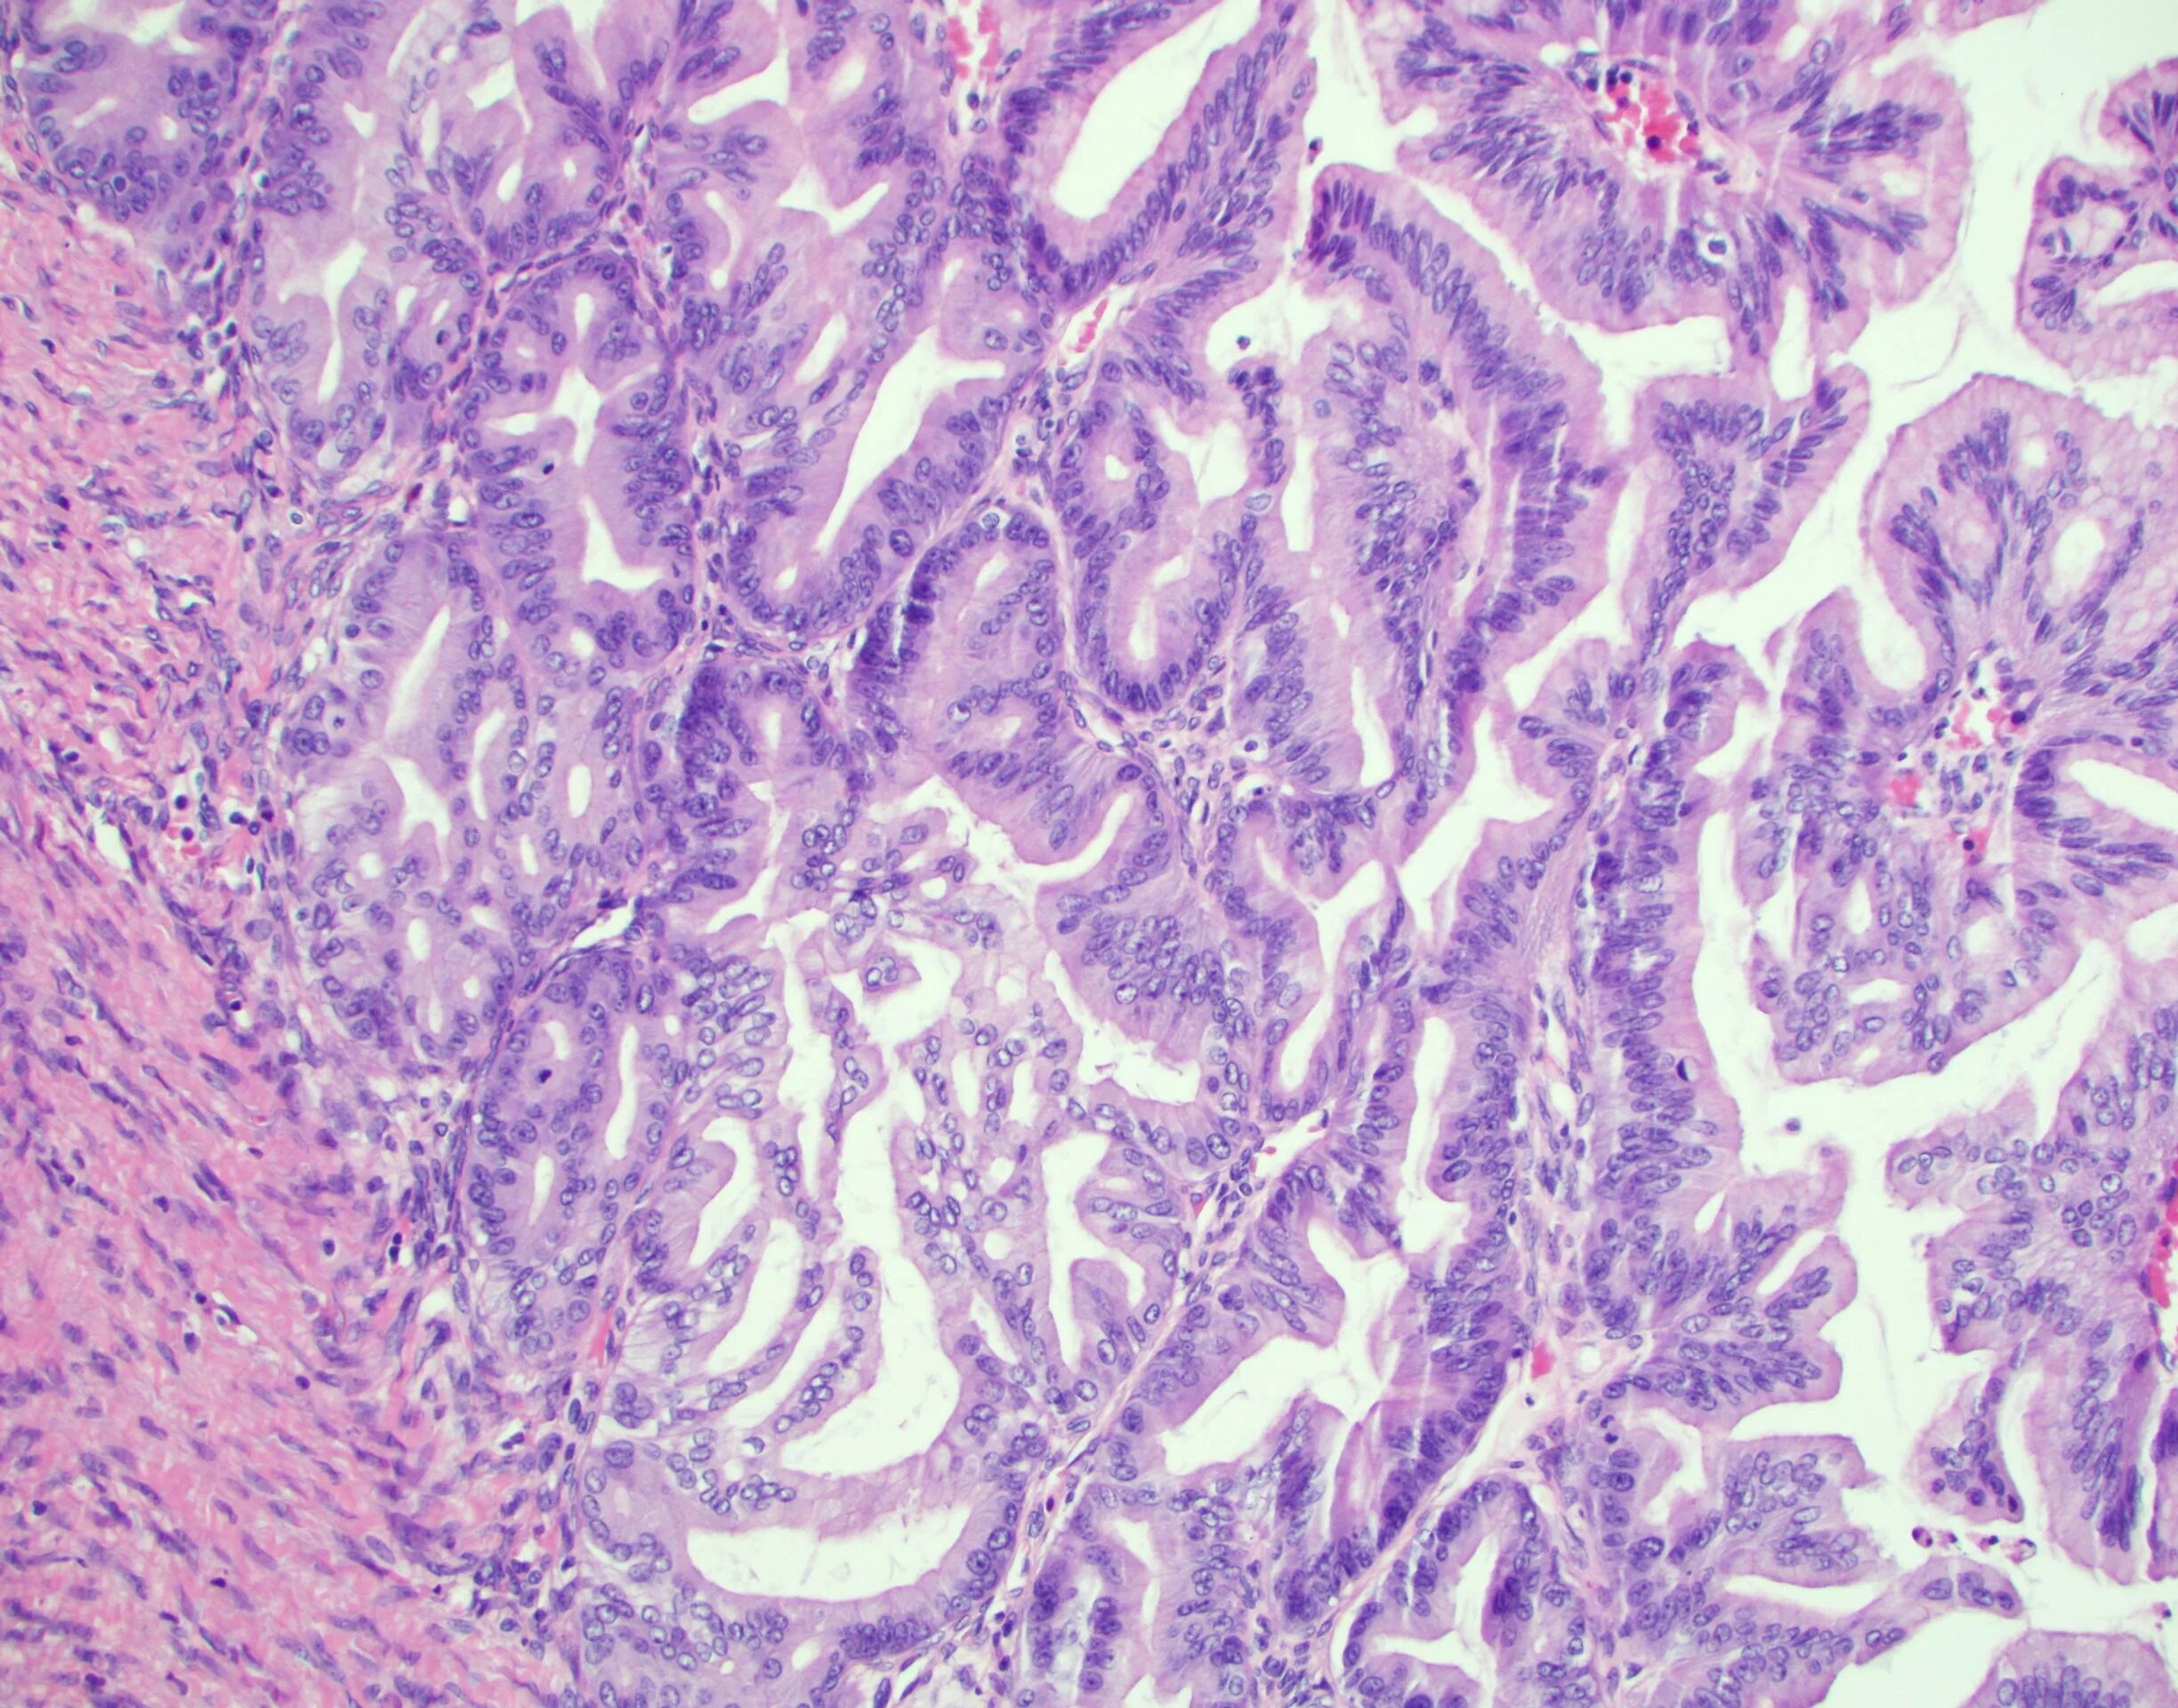

Пограничная гистология